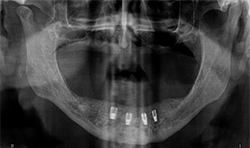

A 69-year-old male presented with an existing maxillary full denture and mandibular fixed partial denture (Tooth Nos. 22-27) with pain and suppuration on abutment teeth supporting the FPD (Figs. 7, 8). All existing abutment teeth were carious and periodontally involved. It was decided with the patient the best treatment option would be to extract the remaining mandibular teeth. All options were presented to patient and patient desired a fixed hybrid for both arches.

Fig.7

Fig.8

All dental records were taken including a CBCT which revealed inadequate bone height for traditional implant lengths. The decision was made to use four Bicon SHORT implants with a TRINIA framework and Ceramage teeth from Shofu.

Fig.9

Fig.10

At a second appointment, four Bicon SHORT implants, three 4 x 6 mm and one 3.5 x 8 mm were placed in the mandibular arch (Figs. 9, 10). After normal healing time, both the maxillary and mandibular arches were fitted with a fixed hybrid prosthesis fabricated from a TRINIA substructure and Ceramage denture teeth. The patient was happy with the fit, function and comfort (Fig. 11).